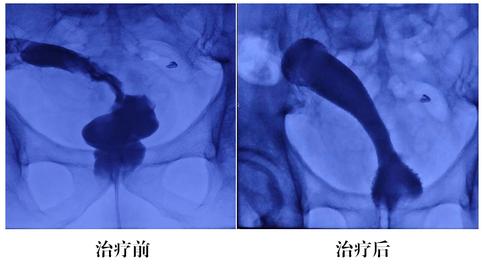

陈军主任及其团队根据患者的既往病史及现有病情,为其制定个体化治疗方案。“患者这种情况一般有两种治疗方法,一种是外科手术,但需要开刀和麻醉,还得给结肠造瘘,术中风险大,且术后还影响生活质量。另一种DSA下行肠道支架置入术,因为介入手术不需要麻醉和开刀,在放射线下经导丝引导穿越乙状结肠狭窄段造影,并选择放置金属肠道支架,手术安全性较高”,陈主任在与患者家属反复沟通,征得同意后,为患者在DSA下顺利行肠道支架置入术,手术取得成功,患者腹痛及肠梗阻症状缓解。

近年来,国内外采用各种金属支架作为肠腔内支撑治疗结直肠恶性狭窄梗阻的报道逐渐增多。对于局部病灶不能切除的原发或复发性大肠癌,已有广泛转移、或不能耐受手术治疗者,肠道支架的过渡性放置,可以替代结肠造瘘术,解除狭窄梗阻,免去患者长期背肛袋之苦,提高其生活质量。该患者内镜已无法通过,只能DSA引导下行肠道造影,明确狭窄部位及范围,完成该项手术。